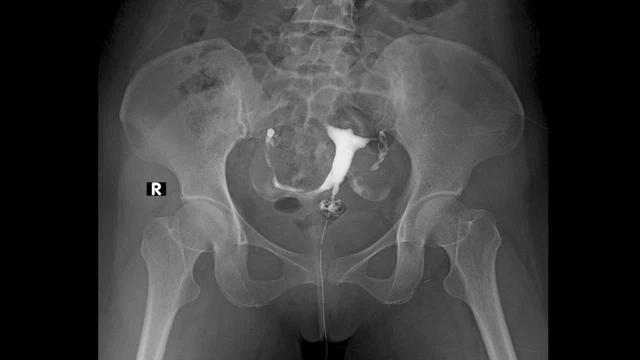

Mang thai là hành trình thiêng liêng mà bất kỳ người phụ nữ nào cũng mong muốn được trải qua. Thế nhưng, không phải ai cũng dễ dàng chạm đến niềm hạnh phúc làm mẹ. Lúc này, việc khám vô sinh nữ trở thành bước quan trọng để tìm ra nguyên nhân và hướng điều trị phù hợp.